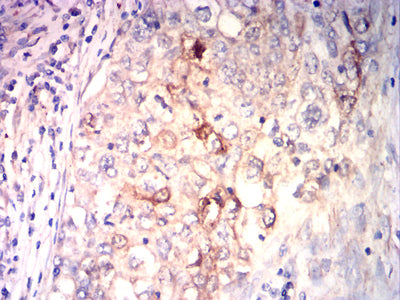

分类: 科研抗体货号: 32249别名: VLA1; CD49a应用: IHC,FCM反应种属: Human